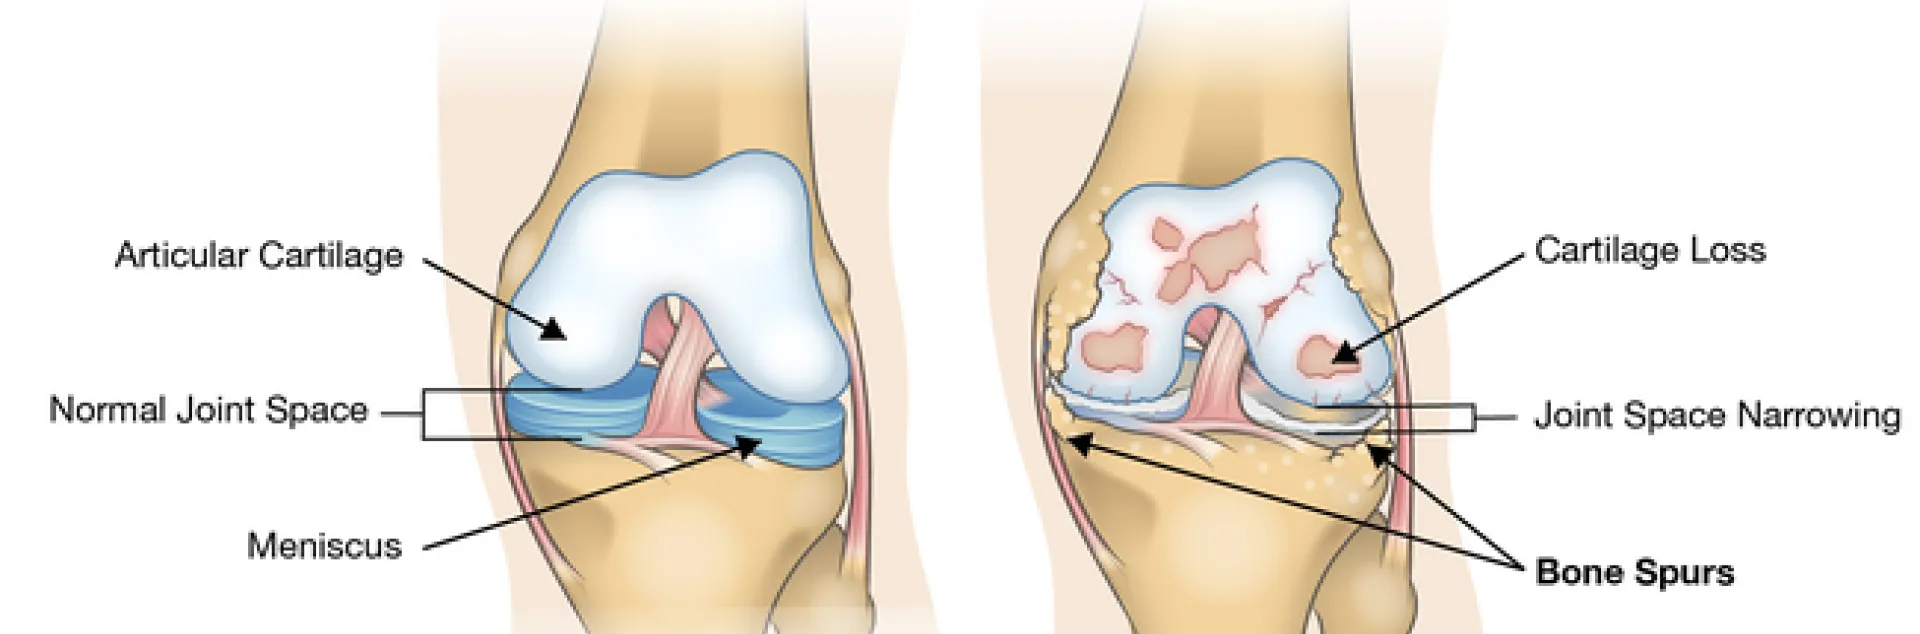

Did you know you have 209 bones in your body? The word bone in Greek is “osteon.” It is commonly used as a prefix to refer to issues of the bones. Each bone has two ends and where they meet another bone, that area is is called a joint. In Greek, joint = “arthro.” If joints are overused they become inflamed. The Latin suffix for inflammation = “itis.” Each joint can suffer from wear and tear with inflammation pain and that is called arthritis. More specifically, it would be osteo-arthritis.